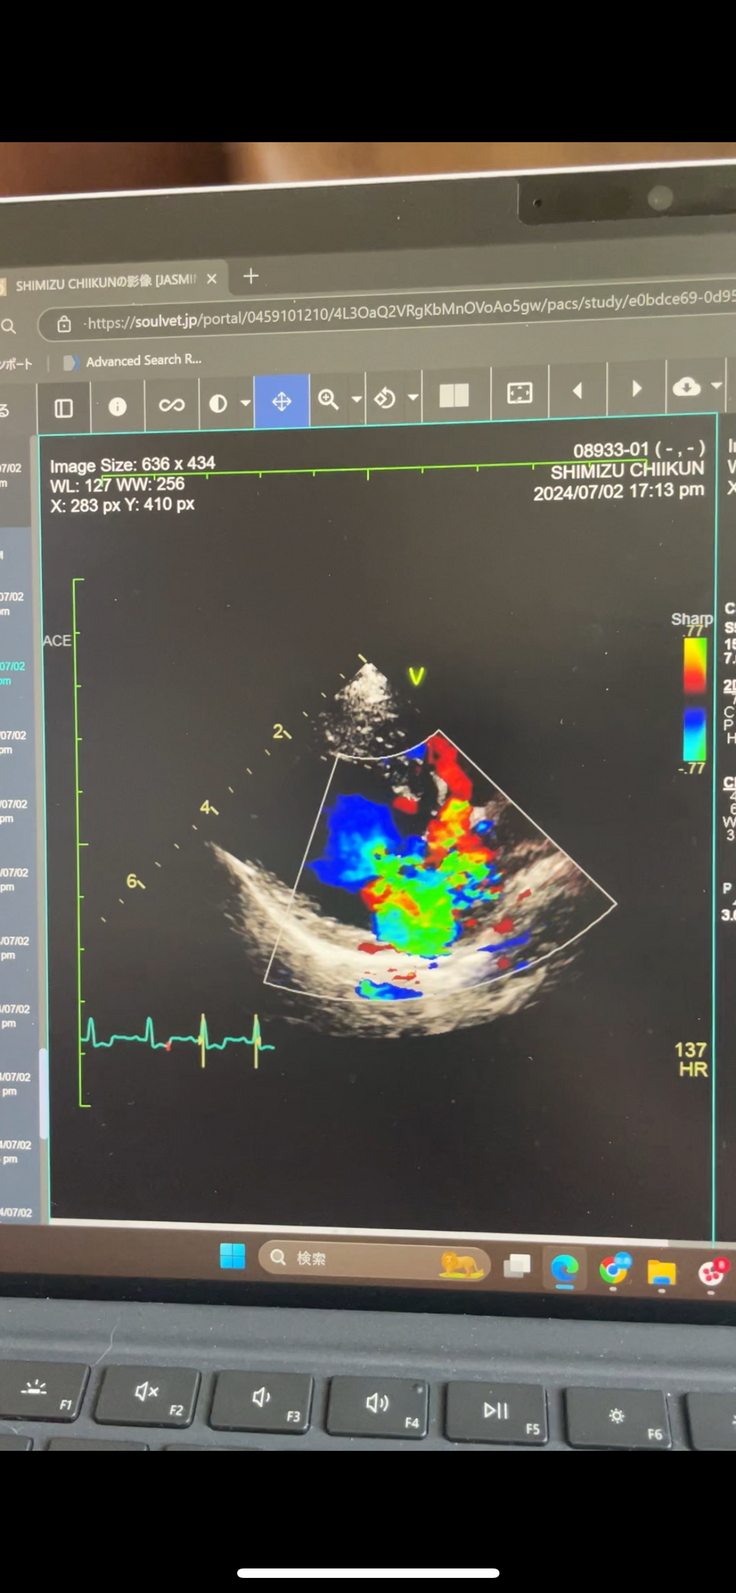

エコー画像ビフォーアフター

チーくんの心臓病(僧帽弁閉鎖不全症)エコー画像、術前と術後の比較です

緑色🟩の部分が逆流する血液です。

心臓の弁が機能せずにガバガバになっているのが分かります